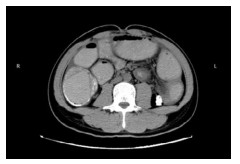

1 资料与方法病例1,患者女,72岁,2020年9月2日因“腹痛3 d”来本院急诊,拟“升结肠肿瘤伴肠梗阻”收住院。半月前因“胆囊结石”在当地医院行腹腔镜下胆囊切除术。本次入院查体:腹部膨隆,右下腹部压痛明显,轻度反跳痛。WBC13.3×109/L, N 84.0%。腹部增强CT提示升结肠管壁不规则增厚伴管腔狭窄,回盲部及远端回肠扩张明显(图 1)。肠镜检查:升结肠肿物,予取病理活检后,在肠道狭窄处行肠梗阻金属支架植入解除梗阻(以维持肠腔的通畅性和减少肠道毒素的进一步吸收)。肠镜病理提示:(升结肠)管状绒毛状腺瘤,部分高级别上皮内瘤变。3 d后复查腹部平扫CT示回盲部及远端回肠原先扩张的肠腔已明显缩小(图 2)。因患者既往有糖尿病史,时常合并胸闷胸痛,心电图示侧壁T波直立,心内科会诊建议行心脏冠脉造影。冠脉造影提示心脏左前降支中段狭窄约百分之八十,远端约百分之九十狭窄。经多学科讨论后认为患者目前急性肠梗阻症状已经缓解,建议可先予冠状动脉药物涂层支架植入术,再予以替格瑞洛口服抗凝治疗,1个月后再次入院行结肠肿瘤手术。患者于2020年10月9日再次入院行腹腔镜下右半结肠癌根治手术,手术过程顺利。术后病理报告:(升结肠)高-中分化腺癌,T3N1M0。患者术后13 d出院,并接受了后续的规律化疗。目前患者恢复良好。

| 图 1 腹部增强CT示回盲部及远端回肠扩张明显、肠腔充满肠道内容物 |